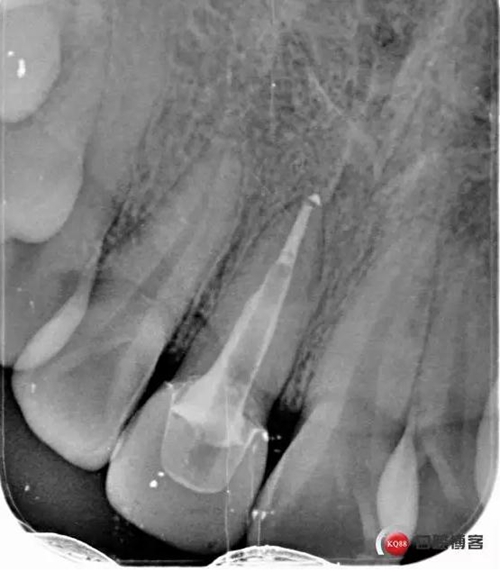

看起來有點(diǎn)頭痛哈,拍片檢查

牙根長度比較號,根充完善。這張片子也可以看出,為什么上次脫落了,樁的深度不夠,而且明顯樁根樁道不匹配,打的樁都沒有到位。

術(shù)后牙片可以看出樁的長度有明顯增加。到達(dá)預(yù)備長度。術(shù)后齦緣高度與鄰牙一致